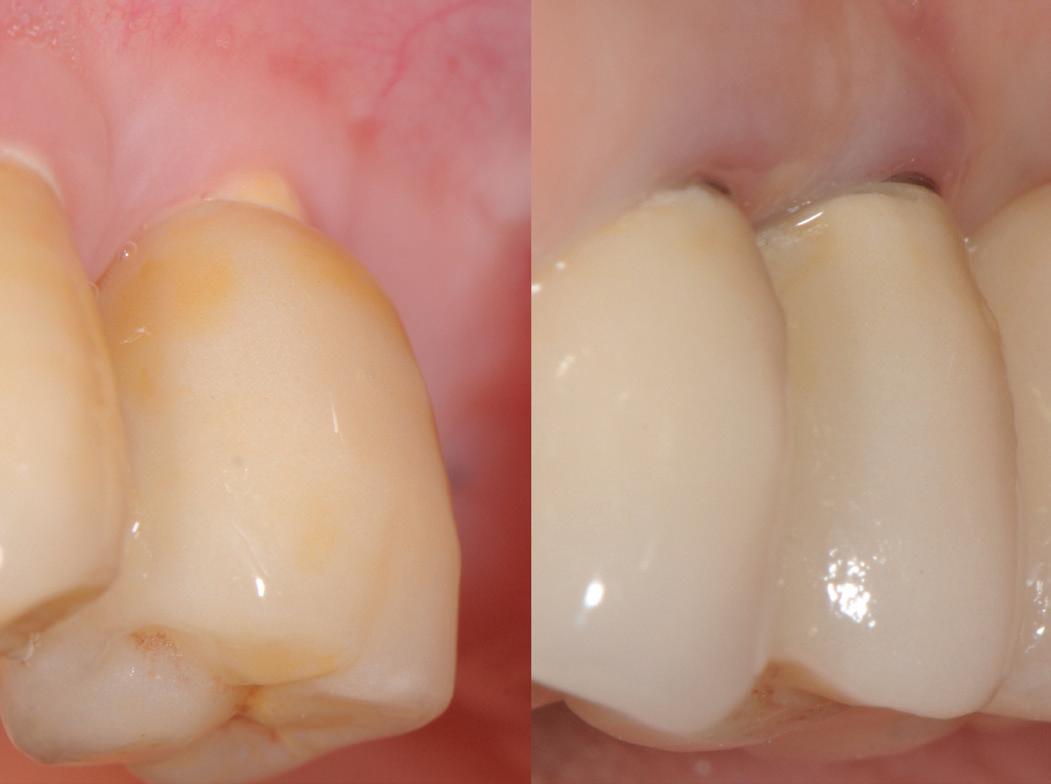

RECONSTITUIREA țesuturilor moi periimplantare. Scopul acestui raport de caz este de a demonstra procedurile chirurgicale utilizate pentru corectarea unui defect al țesuturilor moi periimplantare folosind țesutul moale interdentar în combinație cu tuberozitatea ca locație donatoare de țesut conjunctiv, utilizând o abordare prin tunelizare într-o zonă estetică.

REABILITAREA implanturilor în zona estetică. Acest articol detaliază două cazuri rezolvate prin tehnica extracției parțiale, finalizate fără grefarea compartimentului dintre implant și scut, și monitorizate cinci ani, dovedind stabilitatea volumetrică a țesuturilor moi și dure în timp.

Posibilitatea ca nuanța gri să transpară prin gingie este un posibil dezavantaj al implanturilor de titan. În schimb, datorită culorii albe a dioxidului de zirconiu, această problemă estetică poate fi evitată prin

utilizarea implanturilor ceramice. Desigur, obținerea unei estetici excelente cu implanturile de titan este posibilă în mod curent. Cu toate acestea, o condiție prealabilă pentru un astfel de rezultat este prezența unei mucoase periimplantare cu o grosime de cel puțin 2 mm, care poate împiedica transparența cenușie a titanului. În lipsa acestei grosimi, mucoasa poate fi dublată de o grefă de țesut conjunctiv (recoltată de obicei din palat), necesitând însă o procedură chirurgicală adițională și, prin urmare, o povară suplimentară pentru pacient. Utilizarea bonturilor implantare integral ceramice este o soluție alternativă, dar microdeplasările bontului dur de dioxid de zirconiu pe implantul de titan mai moale pot duce la abraziune și chiar la distrugerea conexiunii implant-bont.

Totuși, ca și în cazul implanturilor de titan, în rare cazuri, și la cele ceramice poate apărea o recesie nedorită cu expunerea umărului implantar. Cu toate acestea, din punct de vedere estetic, această recesie a gingiei inflamate este posibil să fie mult mai bine tolerată de către pacienții preocupați de marginile întunecate ale implanturilor de titan (fig. 2).

În plus, aceste proprietăți bioinerte par să aibă și beneficii în ceea ce privește dezvoltarea periimplantitei și calitatea țesuturilor moi. În comparație cu titanul, dioxidul de zirconiu prezintă acumulare de placă și aderență bacteriană mai redusă, precum și o grosime mai mică a biofilmului depus. Și fluxul sanguin circulant către țesuturile moi este mai asemănător cu cel al unui dinte natural în cazul ceramicii față de titan, care oferă flux sanguin redus semnificativ. Se știe că o circulație sanguină mai bună înseamnă țesuturi moi mai sănătoase, care, la rândul lor, prezintă rezultate estetice îmbunătățite. Deși deocamdată lipsesc dovezile pe termen lung pentru implanturile ceramice, sunt disponibile rezultatele inițiale la 3 și 5 ani, iar tendința, susținută de studii preclinice și experiența clinică, este că dioxidul de zirconiu demonstrează același rezultat - iar în unele studii chiar o pierdere osoasă marginală mai redusă față de implanturile de titan. În această perioadă încă nu s-a descris clinic periimplantită.

Trebuie remarcat, totuși, că în cazul implanturilor ceramice, ca și în al celor de titan, cementita, adică inflamația periimplantară cauzată de reziduurile de ciment, poate duce la periimplantită. În plus, la implanturile din dioxid de zirconiu poate apărea supraîncălzirea la înșurubarea implantului în os, iar suprafețele excesiv de aspre sau poroase ale implantului pot cauza defecte osoase periimplantare din cauza termoconductivității reduse a materialului. Deși sunt necesare mai multe dovezi științifice care să demonstreze o tendință mai scăzută spre periimplantită în cazul implanturilor ceramice, argumentul esențial pentru aceste implanturi bazat pe experiența clinică este starea excelentă și aproape constant lipsită de inflamație a țesuturilor moi periimplantare (fig. 3).